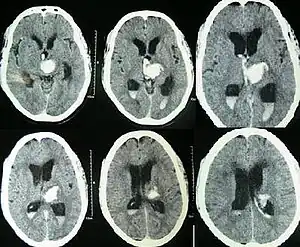

| Hydrocephalus as seen on a CT scan of the brain. The black areas in the middle of the brain (the lateral ventricles) are abnormally large and filled with fluid. | |